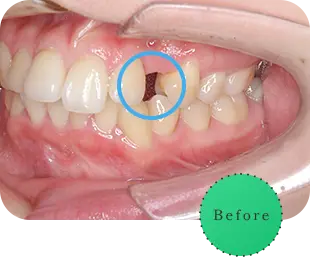

主訴

前歯をきれいにしたい

治療期間

8か月

治療費

40万円

治療内容

右上2番をマウスピース矯正で移動してラミネートべニアにて修復

治療のリスク

【マウスピース】

矯正装置を初めて装着した時は、違和感や圧迫感、疼痛などを感じる場合があります。

歯根吸収や歯肉の退縮が起こる場合があります。

1日の装着時間が長いため、口内清掃不足だとむし歯・歯周病のリスクが高くなります。

歯の移動後に保定装置(リテーナー)の使用が不十分の際は、後戻りが生じる場合があります。

マウスピースの装着時間が少ないと治療期間が長引く場合があります。

【セラミック】

咬み合わせによっては、セラミックが欠ける可能性があります。